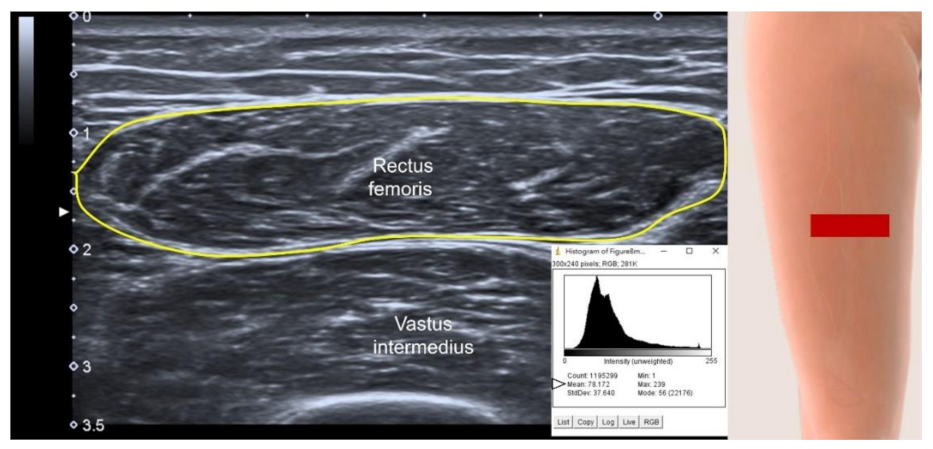

3.4.3. US parameters in B-Mode

3.4.4. Muscle Stiffness Measurement by Sonoelastography